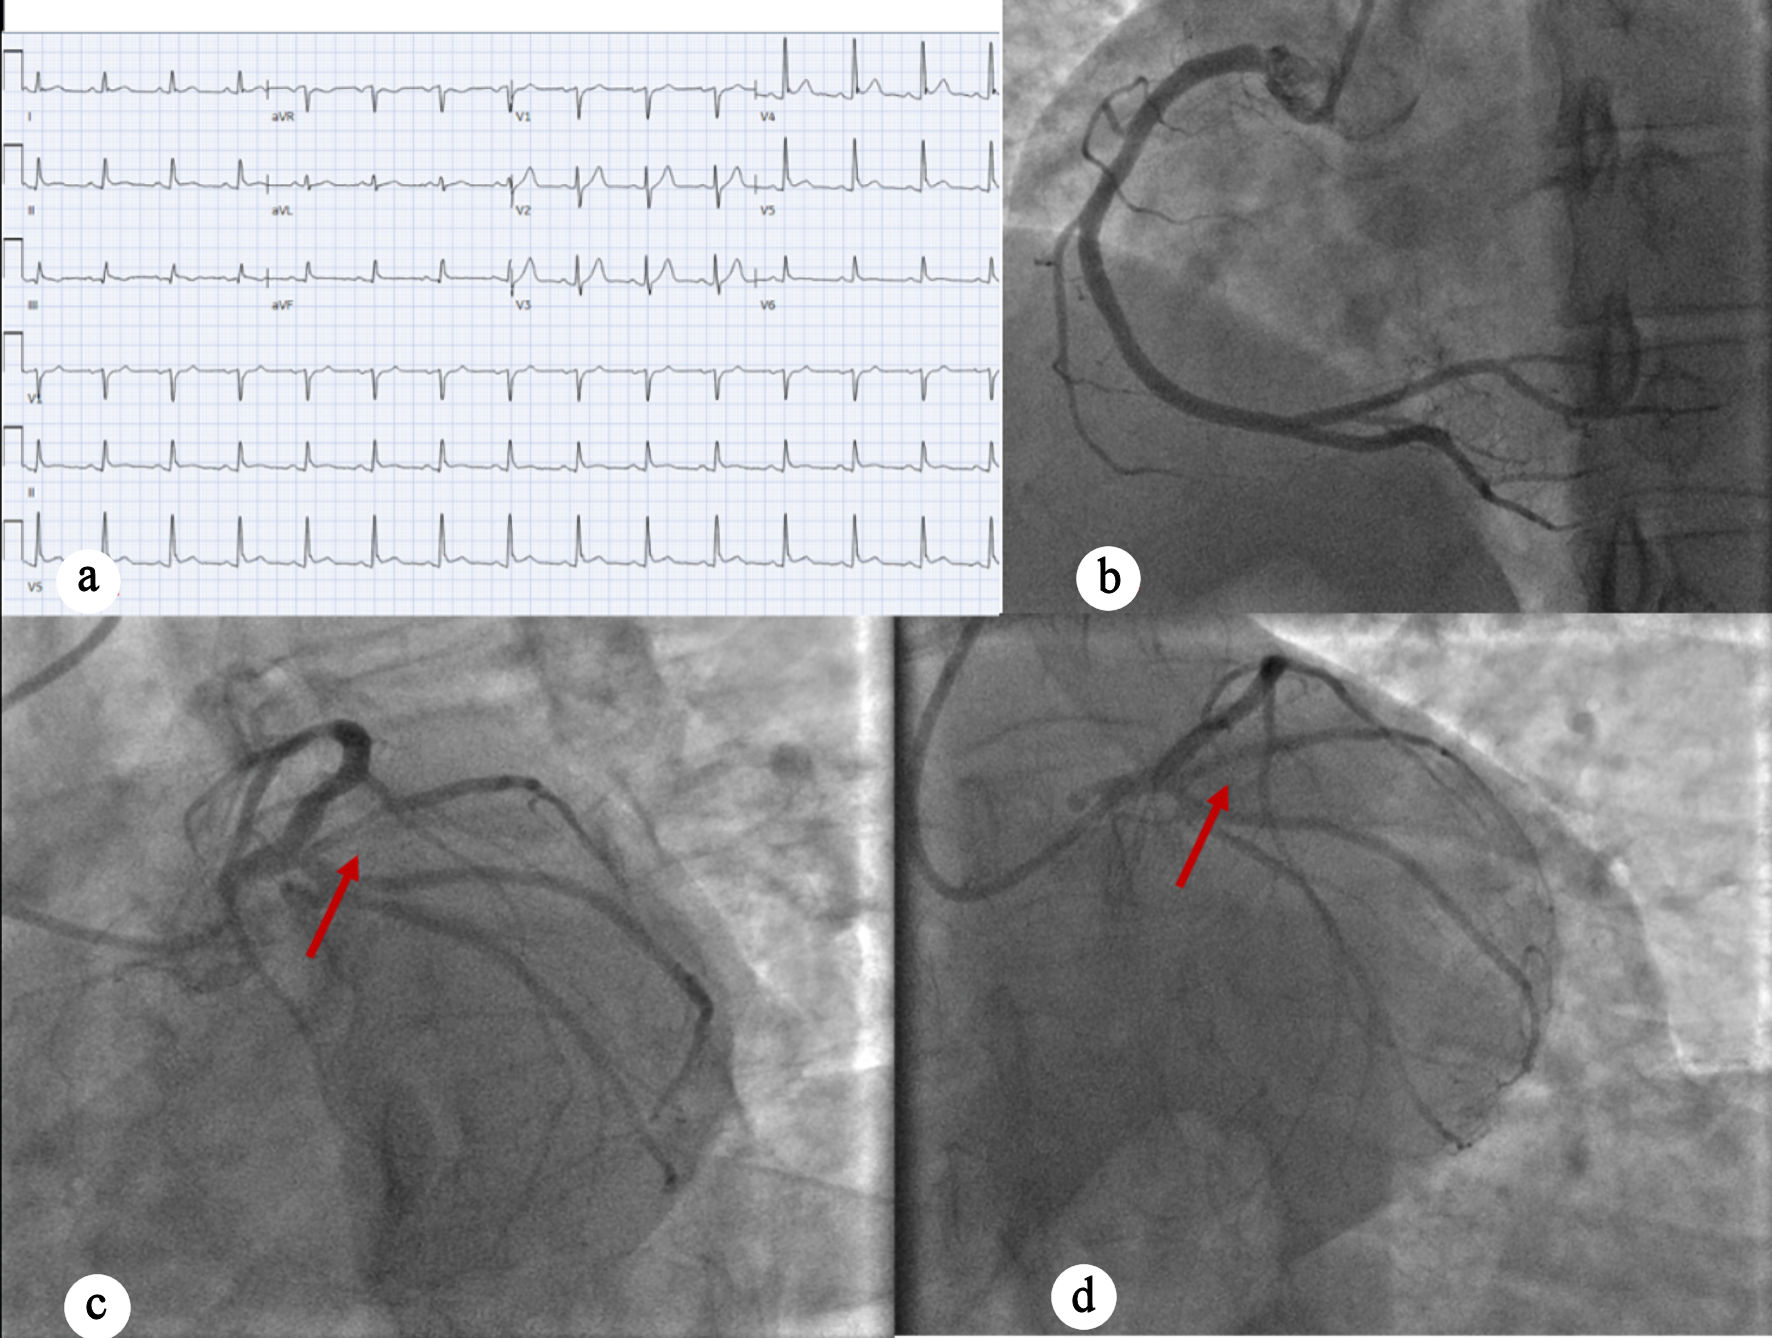

A 51-year-old man with a history of prediabetes, asthma, and obstructive sleep apnea presented with intermittent burning chest pain lasting 2 weeks. The pain was exertional, worsened with emotional distress, radiated to his throat and left scapula, and improved with rest. The patient’s family history is significant for MI in his father at age 67. The social history revealed recent occupation-related stress, with no history of substance use disorder. On the day of admission, his symptoms did not improve with rest or omeprazole. In the emergency department (ED), the patient was hemodynamically stable, and troponins were elevated at 0.6 ng/mL to 1.96 ng/mL (normal < 0.10 ng/mL). EKG showed sinus rhythm at a heart rate of 60 beats per minute without clear ischemic changes (Fig. 1a). Cardiology was consulted due to elevated troponin. Bedside point-of-care ultrasonography (POCUS) showed no overt regional wall motion abnormalities; however, due to the concerning clinical presentation and rising troponin levels, the interventional cardiology (IC) team was activated. The patient underwent left heart catheterization (LHC), which showed three-vessel obstructive coronary artery disease (CAD) with a proximal LCX total/subtotal thrombotic occlusion. Percutaneous coronary intervention (PCI) with placement of a drug-eluting stent (DES) was successfully performed (Fig. 1b–d). Left ventricular (LV) systolic function was preserved, with a low LV end-diastolic pressure of 5 mm Hg. The patient was admitted to the cardiac critical care unit (CCU) for monitoring, and transthoracic echocardiogram (TTE) the following day revealed normal LV size with preserved ejection fraction (EF) of 55–60%, mild inferolateral hypokinesis, and normal diastolic function. Trace mitral regurgitation was noted. Troponin was trended till downtrend, and the patient was discharged after 12 days with a follow-up with IC team.

Figure 1. (a) EKG showing sinus rhythm with no acute ischemic changes. (b) Left anterior oblique caudal view showing right coronary artery. (c) Left anterior oblique caudal view showing complete occlusion of left circumflex artery (red arrow). (d) Post-PCI perfusion of the left circumflex artery (red arrow). EKG: electrocardiogram; PCI: percutaneous coronary intervention.